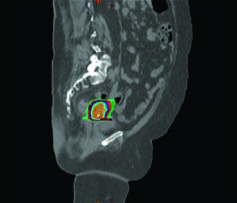

- Cone-beam CT (CBCT) diário: permite identificar o estado de enchimento retal e vesical em comparação à simulação. Com expansão de PTV baseada em modelo de forma e guia diário por CBCT, a cobertura do alvo dentro da isodose de 95% demonstra-se excelente.

- Monitoramento da variação: a Figura 24.1 ilustra um caso real em que mudanças no enchimento vesical e retal deslocaram o fundo uterino para fora do PTV — exatamente o tipo de evento que o CBCT pré-tratamento detecta e permite corrigir.

Na prática diária, o CBCT oferece o melhor equilíbrio entre informação anatômica e viabilidade logística. A dose adicional de imagem é clinicamente aceitável quando comparada ao risco de subdosagem tumoral por deslocamento não detectado.